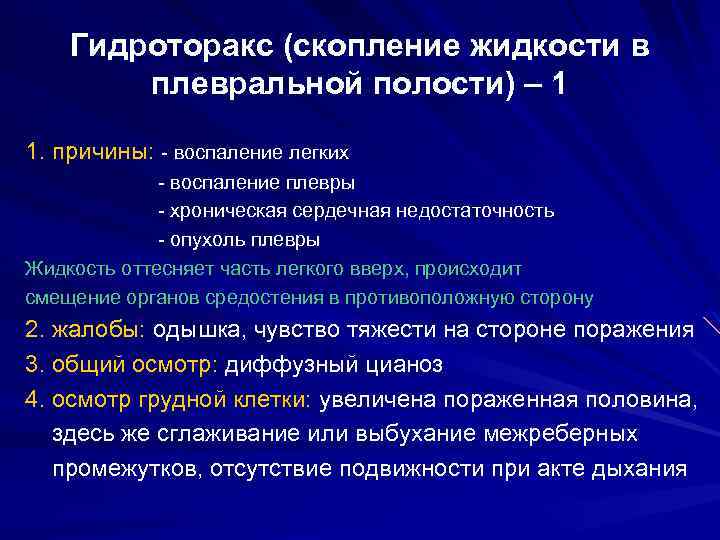

Симптомы и причины скопления воды в легких